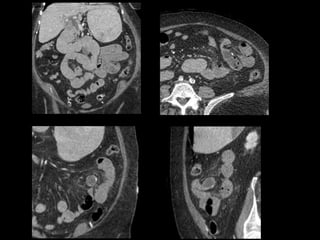

This document describes four patient cases seen by different doctors, including a 72-year-old female with abdominal pain, a 42-year-old female with abdominal pain and bloody diarrhea, a 37-year-old male with chest pain and vomiting of digested blood, and a 67-year-old male with an abnormal heart ultrasound.